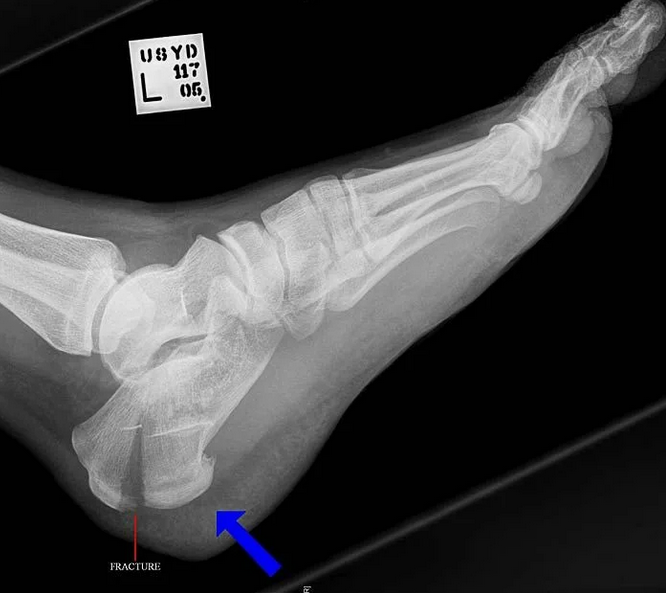

В случае перелома шейки бедра компания МосРентген Центр госпитализирует в Склиф для эндопротезирования.